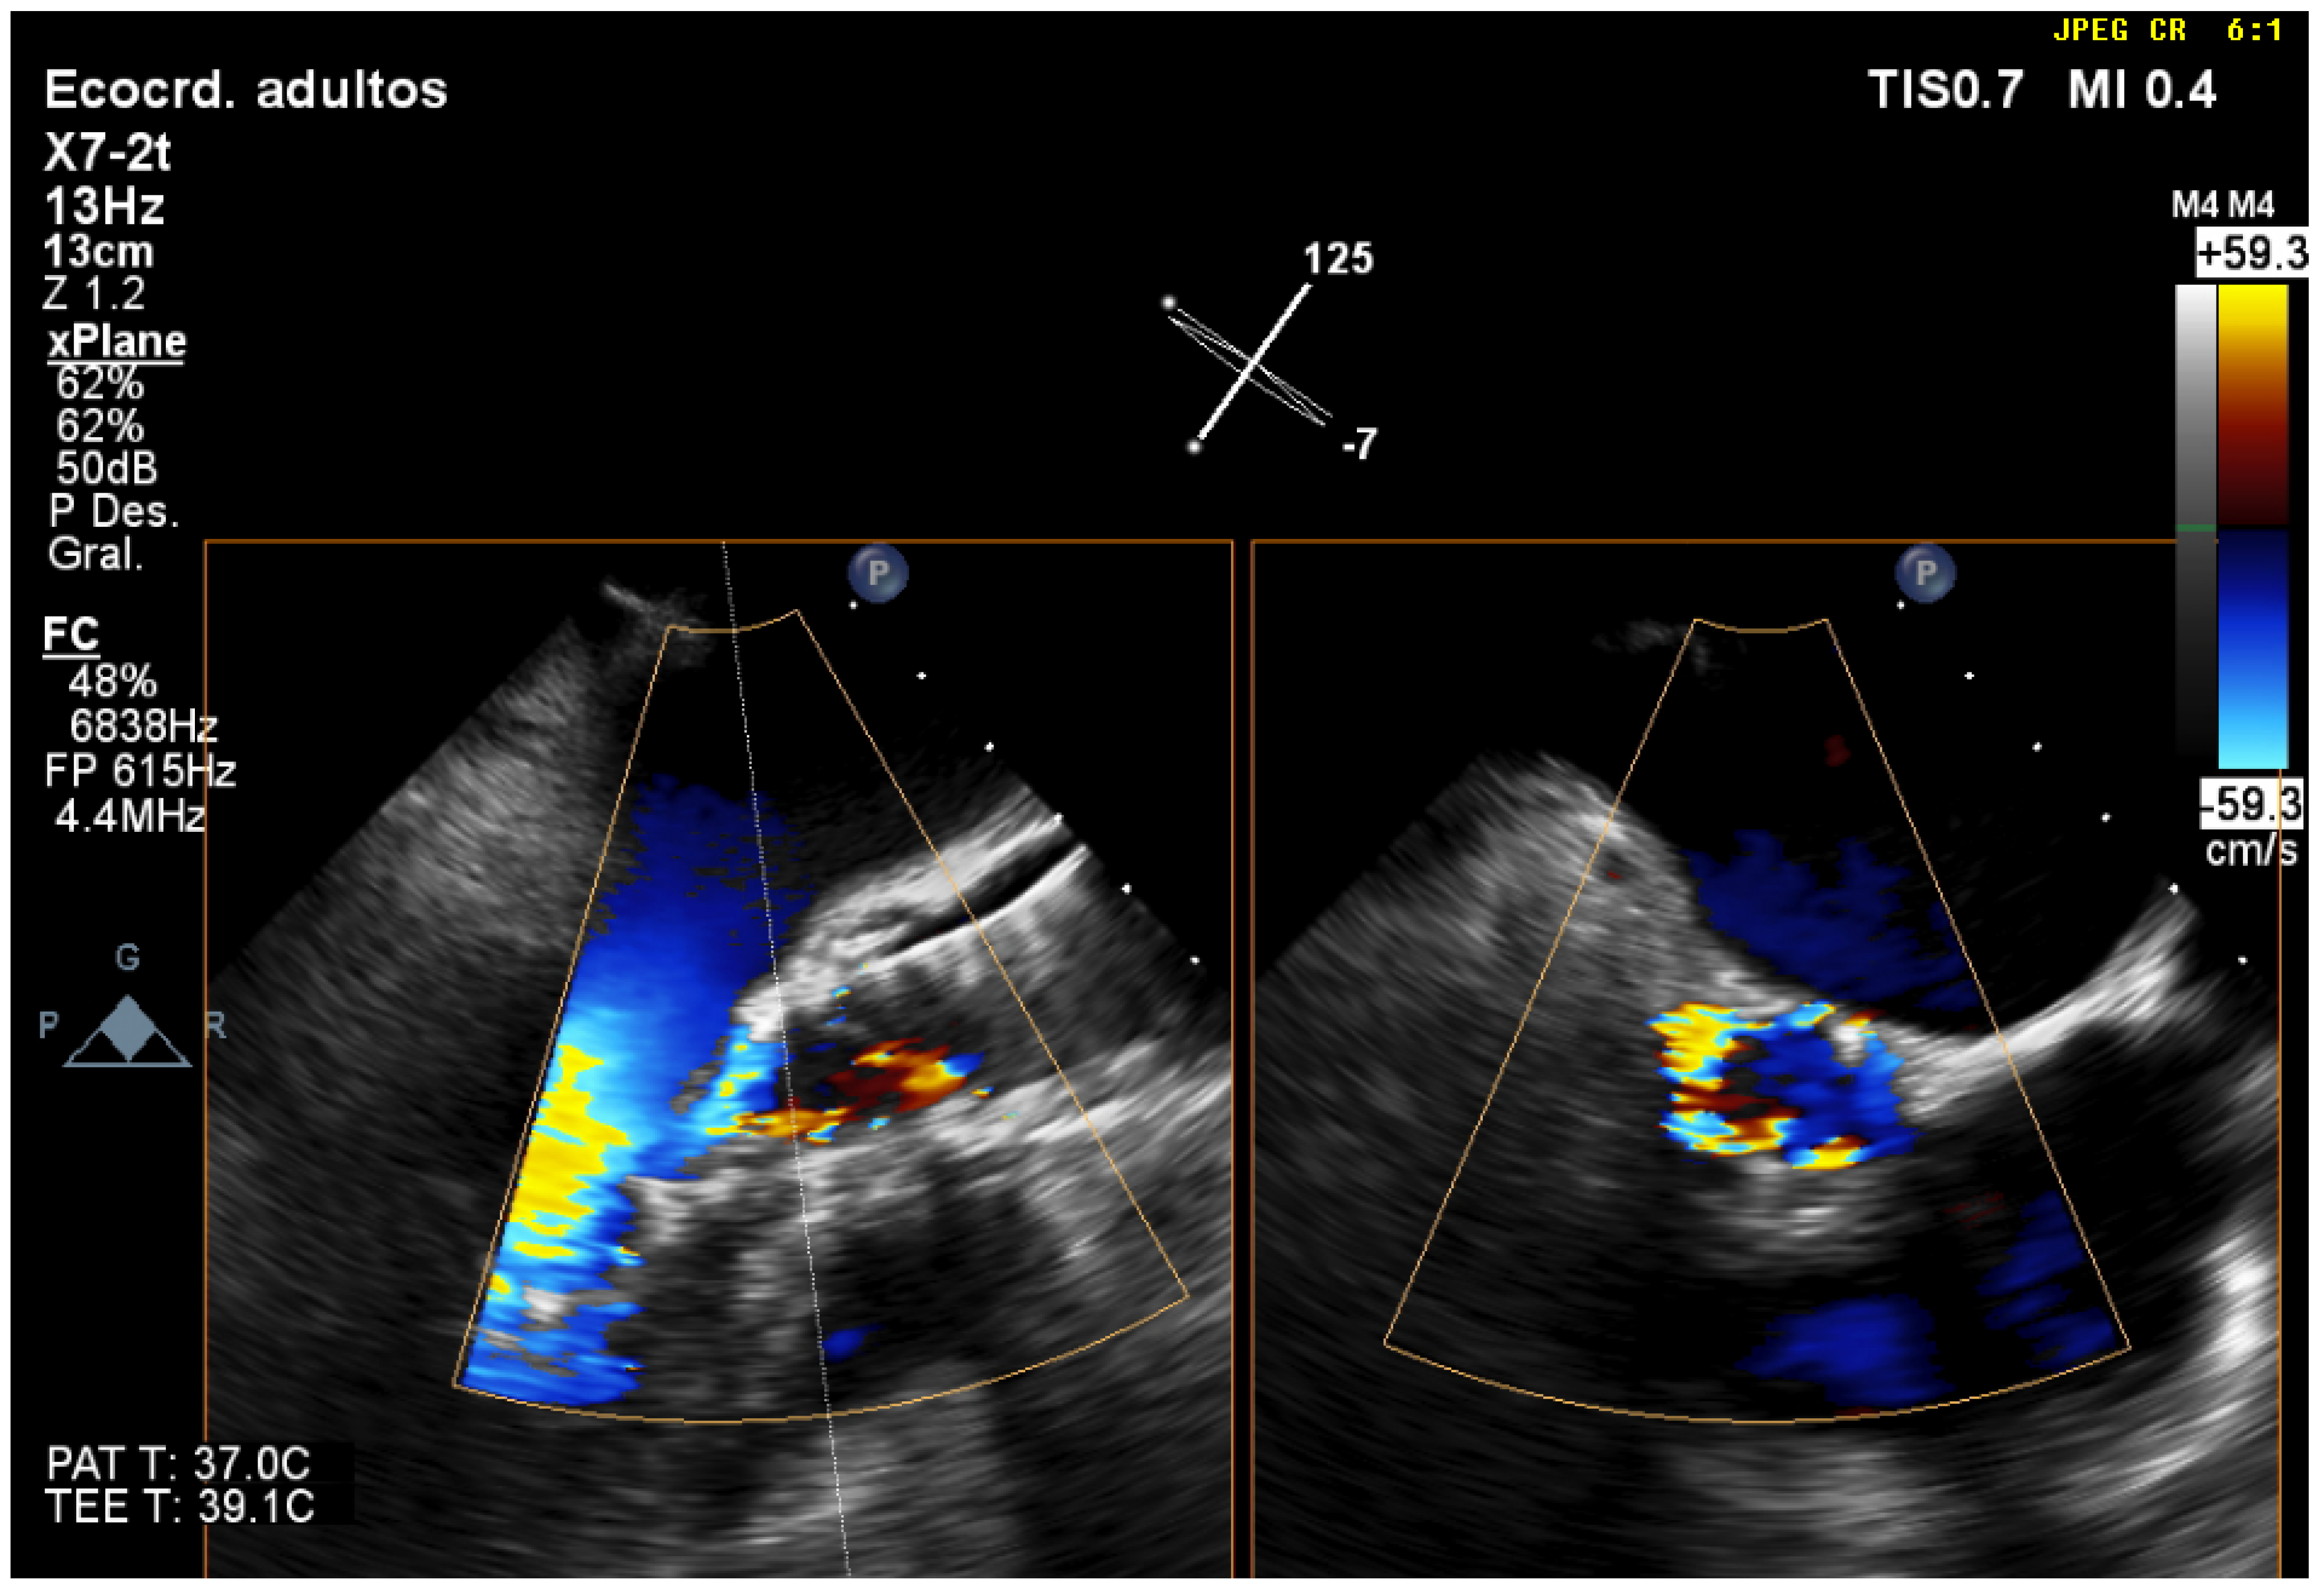

Three-dimensional TEE makes it possible to quantify aortic regurgitation more precisely. Visualization of two orthogonal planes with the biplanar color method localizes the jet and evaluates the mechanism and severity of aortic regurgitation more accurately than 2D-TEE (Figure 6 and Video S17). Planimetry of the vena contracta area by 3D-TEE facilitates a better classification of moderate regurgitation [18]. Another possible complication of the procedure is embolization of the prosthesis, which is a rare and serious complication that must be diagnosed quickly (Video S18). Sometimes there is a displacement of the prosthesis towards the LVOT, which can cause mitral regurgitation due to restriction of the anterior mitral leaflet. Displacement towards the aorta can cause occlusion of the coronary ostia and, as a consequence, ventricular dysfunction. The presence of QRS widening or hemodynamic deterioration with abnormalities in segmental contractility after expansion of the prosthesis should alert physicians to possible compromise due to coronary artery obstruction. In one study, 70% of patients with coronary obstruction had a left main coronary artery height < 12 mm and a maximum aortic root diameter < 30 mm. It is also important to evaluate the aortic root, since it could have increased in thickness due to an intramural aortic hematoma (Video S19) or an aortic dissection. The sudden appearance of pericardial effusion (Video S20) should alert physicians to possible ventricular perforation or rupture of the aortic annulus.

Figure 6.

Evaluation of post-TAVR perivalvular aortic regurgitation using 3D-TEE in biplanar mode (X-plane). In the short axis, it is observed that regurgitation covers more than 30% of the circumference, which corresponds to severe regurgitation.